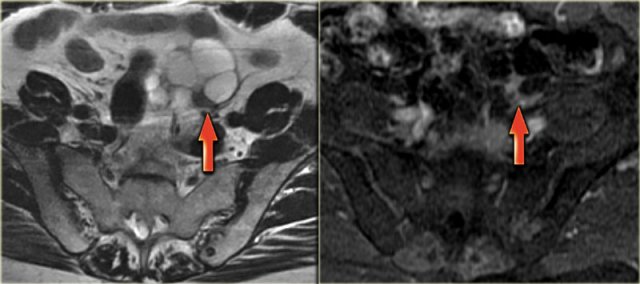

Cystic metastases to the ovaries

While metastases to the ovary are most commonly solid - such as for example Krukenbergs metastases - cystic ovarian metastases do occur.

The CT image shows complex cystic masses in both ovaries.

While a serous cystadenocarcinoma may very well be bilateral, they are more often unilocular than multilocular.

Barely visible is part of a circumferential colorectal cancer (blue arrow).

Clearly visible are cystic implants on the peritoneal reflection (red arrow). These were cystic ovarian metastases of a colorectal cancer. This is an uncommon finding.